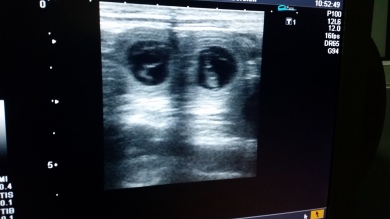

14.07.2015 - 28. Trächtigkeitstag

Noch ist nicht viel zu sehen, aber der Ultraschall hat es bestätigt ... unser B-Wurf ist unterwegs.

Die Welpen sind ca. 4 cm groß. Im Ultraschall sind deutliche Bewegungen sichtbar.